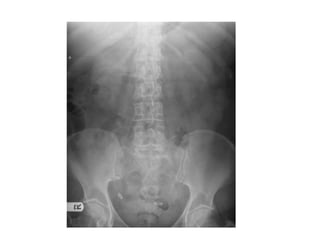

• 40 year old

female with

abdominal pain

and vomiting

• 40 yearold female with abdominal pain and vomiting